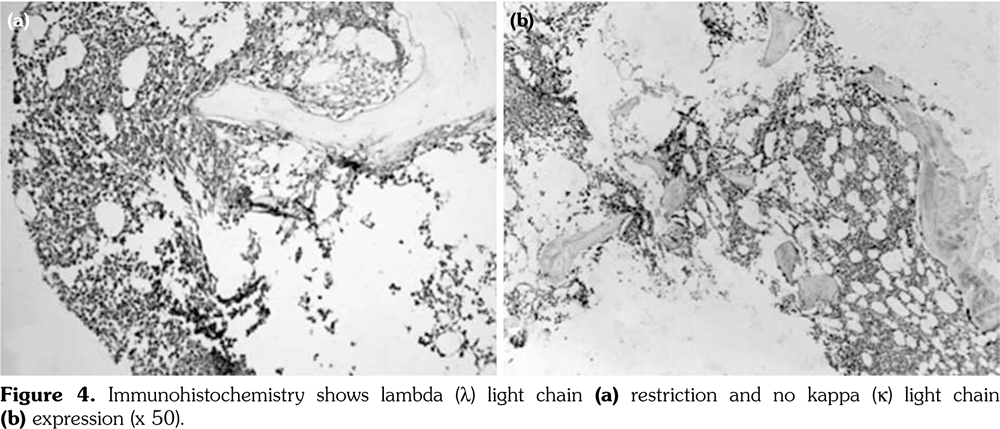

However, two years after the diagnosis of basal-cell carcinoma, the patient was re-admitted to the hospital due to complaints of feebleness, palpitation and cough lasting for 10 days. Laboratory analysis showed an increased white blood cell count of 20x109 L (NR 4-10x109/L), decreased red blood cell count of 1.28x1012/L (NR 3.5-5.0x1012/L), and platelet count of 45x109/L (NR 100-300x109/L). Serum electrophoresis revealed monoclonal protein of 68.24%. The urinary lambda (l) light chain was 0.186 (NR <0.05). Bone marrow biopsy revealed diffuse fibrosis with collagen deposition, heavy infiltration of neoplastic plasma cells (CD138, PC positive), and l light chain restriction (Figure 2-4) with a total ratio of 66% for original and naive plasma cells. Hence, the diagnosis of l plasmacytic leukemia was confirmed. However, our patient rejected to undergo further evaluation and treatment due to personal reasons.